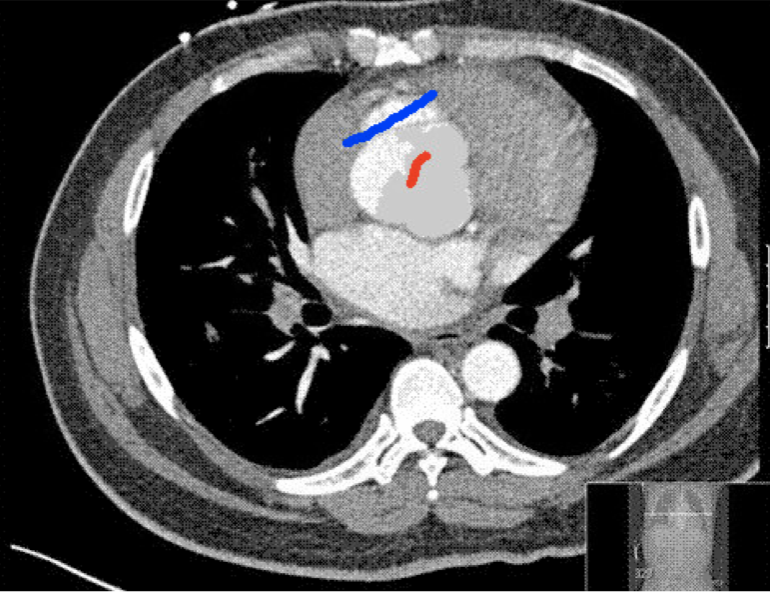

Four sets of test results are shown below. In Test 1 we compare models M1 – M6 to the proposed model M7 for two images which are hard to segment. The first is a CT scan from which we would like to segment the lower portion of the heart, the second is an MRI scan of a knee and we would like to segment the top of the Tibia. See Figure 9 for the test images and the marker sets used in the experiments. In Test 2 we will review the sensitivity of the proposed model to the main parameters. In Test 3 we will give several results achieved by the model using marker and anti-marker sets. In Test 4 we show the initialisation independence and marker independence of the Geodesic Model on real images.

In this test we give the segmentation results for models M1 – M7 for the two challenging test images shown in Figure 9. The marker and anti-marker sets used in the experiments are also shown in this figure. After extensive parameter tuning, the best final segmentation results for each of the models are shown in Figures 10 and 11. For M1 – M4 we obtain incorrect segmentations in both cases. In particular, the results of M2 and M4 are interesting as the former gives poor results for both images, and the latter gives a reasonable result for Test Image 1 and a poor result for Test Image 2. In the case of M2, the regularisation term includes the edge detector and the distance penalty term (see (4)). It is precisely this which permits the poor result in Figures 10(b) and 11(b) as the edge detector is zero along the contour and the fitting terms are satisfied there (both intensity and area constraints) – the distance term is not large enough to counteract the effect of these. In the case of M4, the distance term and edge detector are separated from the regulariser and are used to weight the Chan-Vese fitting terms (see (9)). The poor segmentation in Figure 11(b) is due to the Chan-Vese terms encouraging segmentation of bright objects (in this case), weighting enforces these terms at all edges in the image and near . In experiments, we find that M4 performs well when the object to segment is of approximately the highest or lowest intensity in the image, however when this is not the case, results tend to be poor. We see that, in both cases, models M5 and M6 give much improved results to M2 and M4 (obtained by incorporating the geodesic distance penalty into each). The proposed Geodesic Model M7 gives an accurate segmentation in both cases. It remains to compare M5, M6 and M7. We see that M5 is a non-convex model (and cannot be made convex [39]), therefore results are initialisation dependent. It also requires one more parameter than M6 and M7, and an accurate set to give a reasonable area constraint in (4). These limitations lead us to conclude M6 and M7 are better choices than M5. In the case of M6, it has the same number of parameters as M7 and gives good results. M6 can be viewed as the model M7 with weighted intensity fitting terms (compare (18) and (30)). Experimentally, we find that the same quality of segmentation result can be achieved with both models generally, however M6 is more parameter sensitive than M7. This can be seen in the parameter map in Figure 12 with M7 giving an accurate result for a wider range of parameters than M6. To show the improvement of M7 over previous models, we also give an image in Figure 13 which can be accurately segmented with M7 but the correct result is never achieved with M6 (or M3). Therefore we find that M7 outperforms all other models tested M1 – M6.

(i) (ii) (iii) (iv)